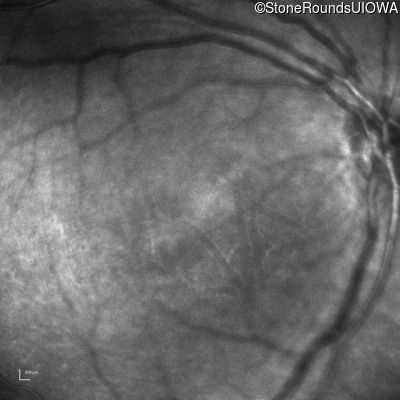

XL Retinoschisis (IIIB1)

Age at visit: 6 years

This 6 year old boy began sitting very close to the television at age 2.

Diagnosis & molecular findings

XL Retinoschisis RS1 Tyr93Stop TAT>TAG   XL